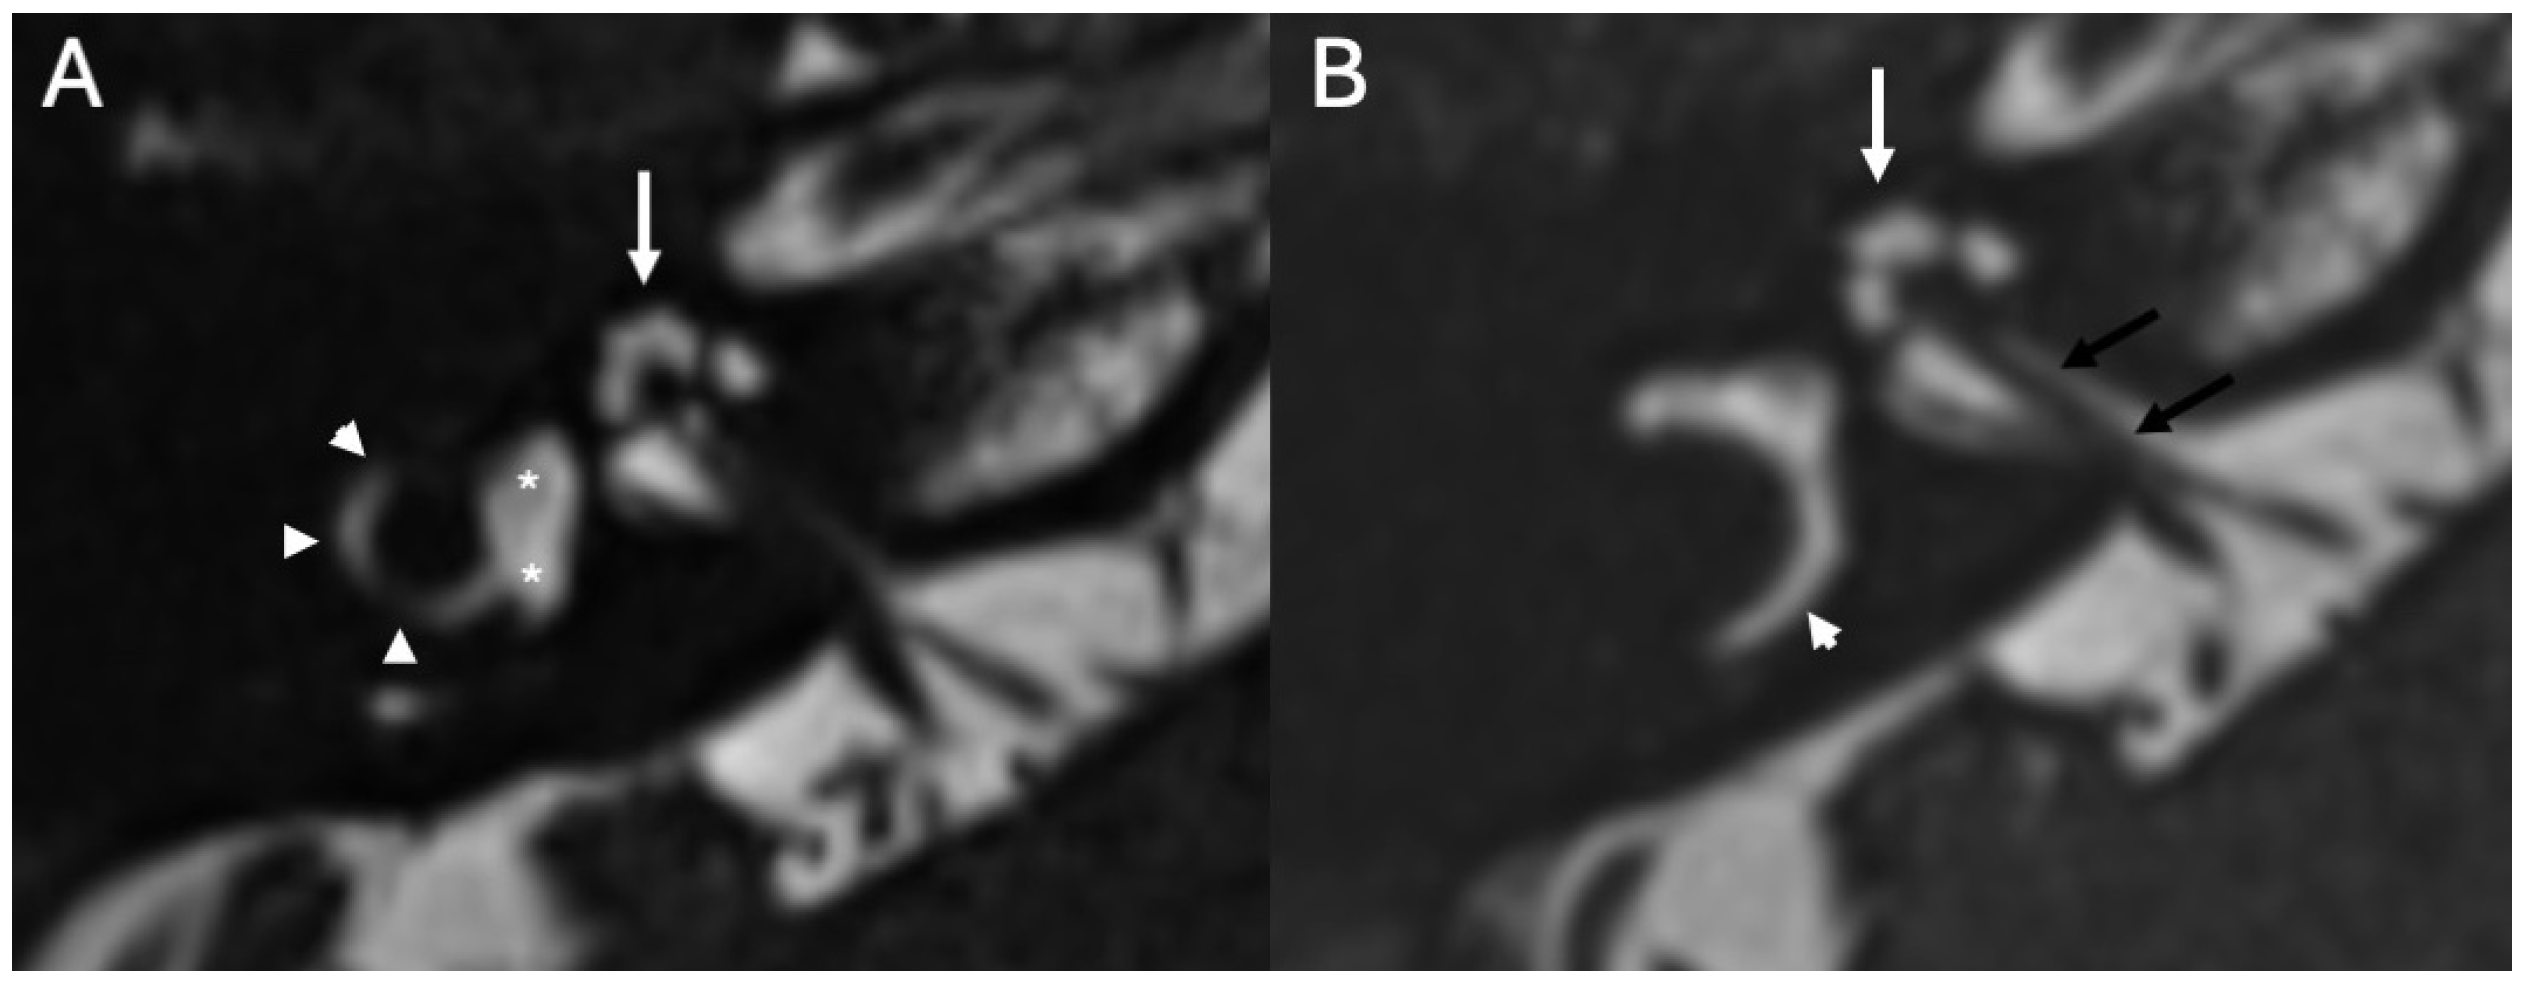

3.2. Bony Dehiscence

3.3.1. Imaging

3.3.2. Complications